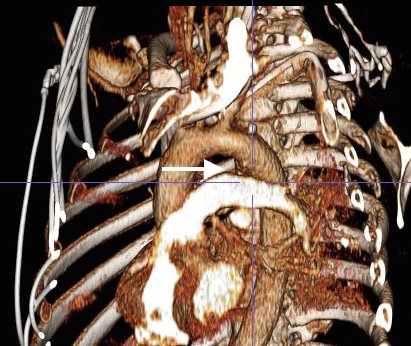

This patient presents with lifestyle limiting claudication and an absent right femoral pulse. ABI is moderately reduced on the right to 0.57, and he had no rest pain. CTA at our clinic revealed an occluded EIA bracketed by severely calcified and nearly occlusive plaque of the common iliac artery (CIA) and common femoral artery (CFA).

The patient was operated on in a hybrid endovascular OR suite. A right groin incision was made to expose the common femoral artery for endarterectomy and left common femoral access was achieved for angiographic access, but also to place a wire across the occlusion into the common femoral artery.

All actions on the external iliac artery plaque are done with an up-and-over wire, allowing for swift action in the instance that arterial perforation or rupture occur. This event is exceedingly rare when the operation is well planned. With this kind of access, an occlusive balloon or repairing stent graft can be rapidly delivered.